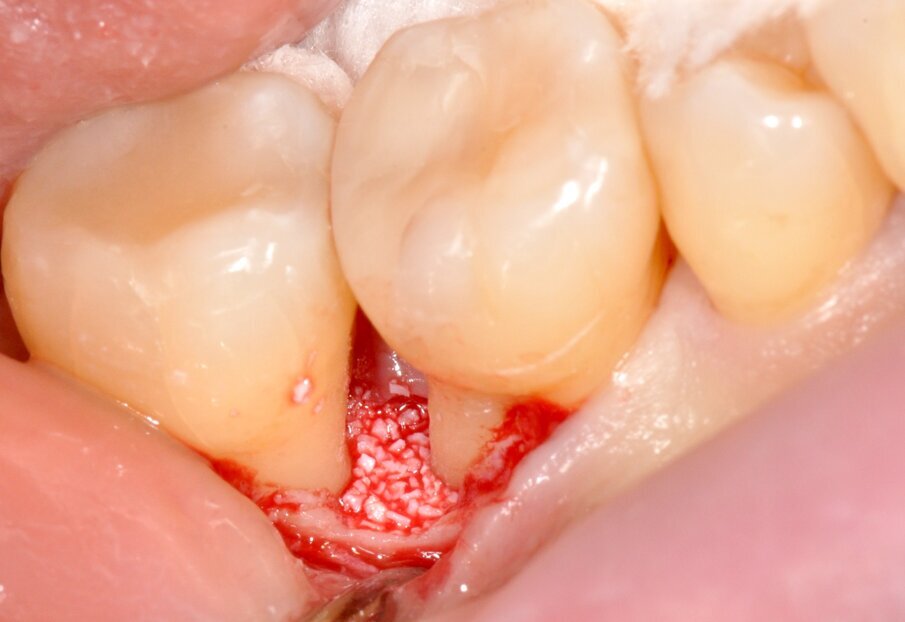

Fig. 11 - Utilizzo di Bio-Oss® per la stabilizzazione del coagulo.

L’esposizione del difetto è eseguita tramite scollamento mini-invasivo a tutto spessore con utilizzo di micro-scollatori e micro-pinzette di tipo “anatomico”. Si effettua rimozione completa del tessuto di granulazione attraverso l’uso di micro-curettes, seguita da debridement ultrasonico intra-operatorio a potenza controllata (Air Flow® Prophylaxis Master EMS®, punta Perio-Slim®) della radice distale dell’elemento 4.6. Valutata la conformazione del difetto, risultante adeguatamente contenitivo, si decide di posizionare un sostituto osseo di origine bovina (Bio-Oss® Geistlich®) ai fini di mantenere una corretta stabilità e sostegno tridimensionale del coagulo6. La sutura è eseguita tramite un punto a materassaio verticale interno modificato con ago di lunghezza 11 mm, morfologia a 3/8 di cerchio e punta di tipo “taper-cut”, filo riassorbibile 5-0 in Acido Poli-Glicolico (PGA).